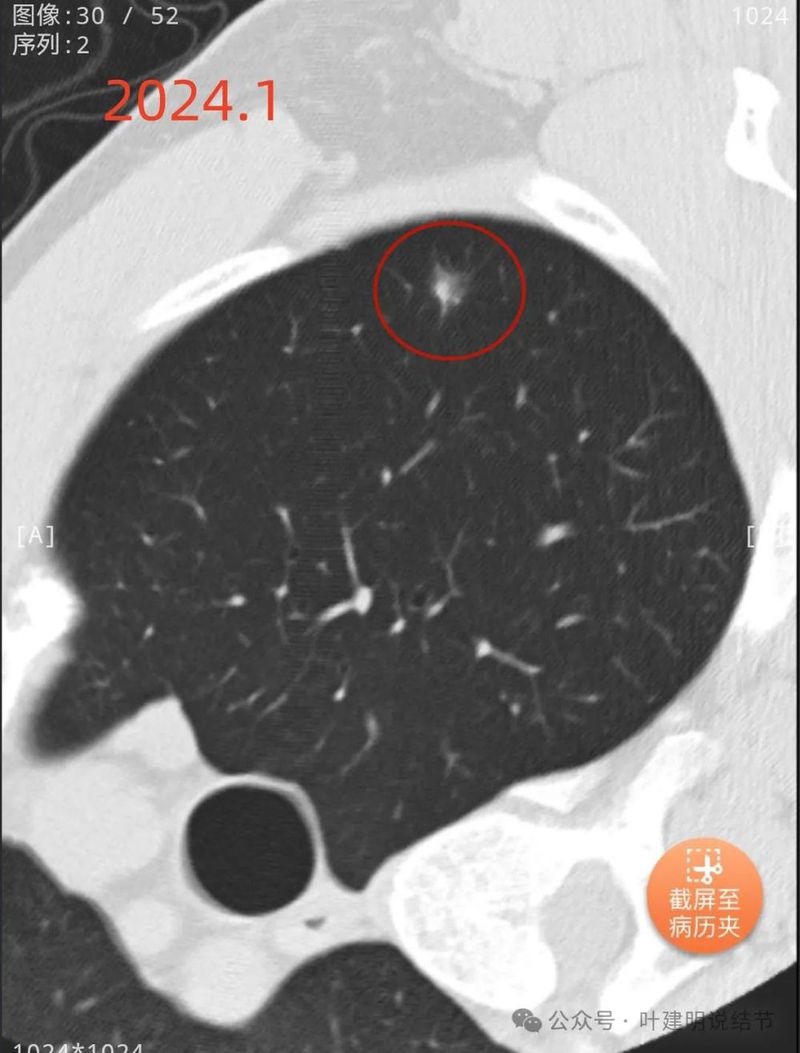

先看不同时间的明显层面截图:

2019年9月时右中叶磨玻璃密度病灶,轮廓与边界清楚,没有实性成分,中间密度稍低,考虑肿瘤范畴的,原位癌或微浸润性腺癌可能性较大。

2023年10月时右侧病灶没有明显进展。